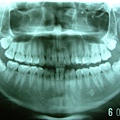

智齒實例4

患者年約19歲,女性,於門診中表示想做矯正治療改善外觀, 因為看起來暴暴的,她不喜歡;經醫師檢查後發現患者的牙弓 太小,加上有4顆智齒爭扎欲出,但卻沒有空間,所以導致牙 齒往前暴的現象。

於是建議患者先將干擾且不易清潔的智齒分次拔除。 再做矯正治療調整咬合,改善外觀。 患者同意了,於是排定時間前來拔牙。

先拔除單側上顎,因牙根無位置生長,所以牙根聚合且彎曲。 傷口恢復良好。

患者再接再勵,將上顎另一側智齒也拔除。 接著下顎也安排時間取出。 目前傷口已完全復原。 |